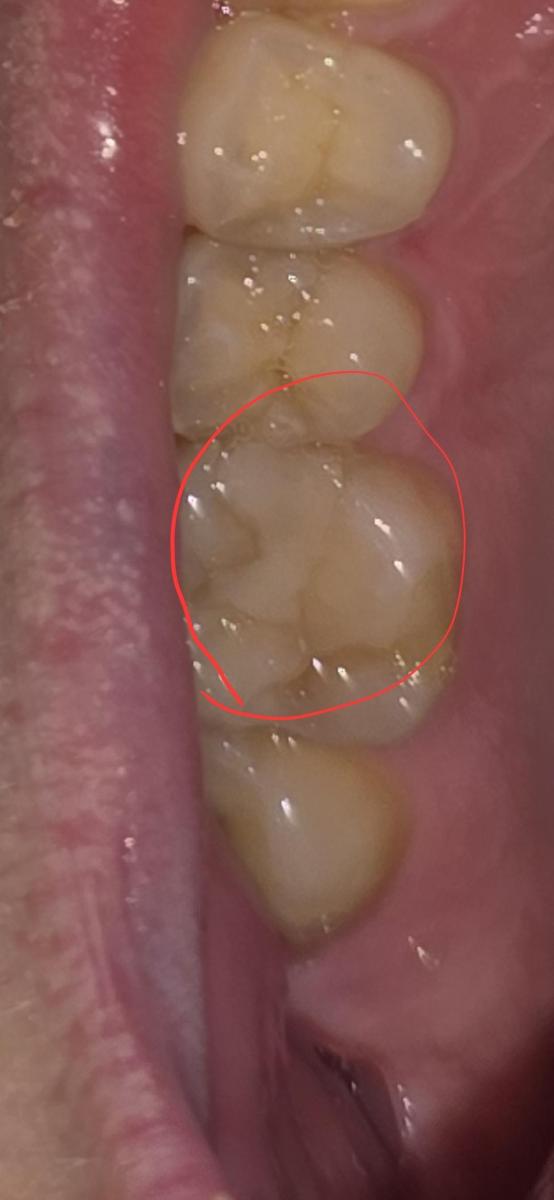

На 6 жевательном зубе справа на верхней челюсти в 2020 году поставлена пломба. Фото прилагаю. На КТ от 2024 года я сам нашел полость под пломбой, это вторичный кариес? Врач который смотрел КТ об этом не упоминал. Еще вопрос зуб же не депульпированный?

Все эти годы зуб не беспокоил. КТ скрины прилагаю.